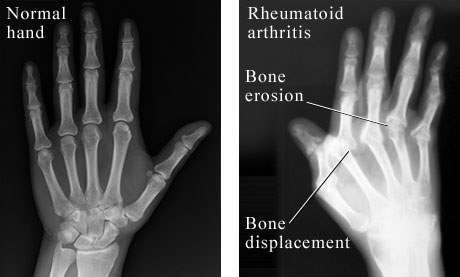

(a) Rheumatoid Arthritis / Arthritis

Rheumatoid arthritis frequently occurs in people under 40 years of age. 75% of them are females. The causes of Rheumatoid arthritis are thought to be:

Treatment of Rheumatoid Arthritis must start as early as possible after diagnosed. Golden period will be within 3 years. If you waited until all the joints becoming deformed, these deformities are irreversible. Rheumatoid Arthritis affects all of the body’s synovial joints. People with Rheumatoid Arthritis contains antibodies called “Rheumatoid Factors” a finding that can aid in the diagnosis of the condition.